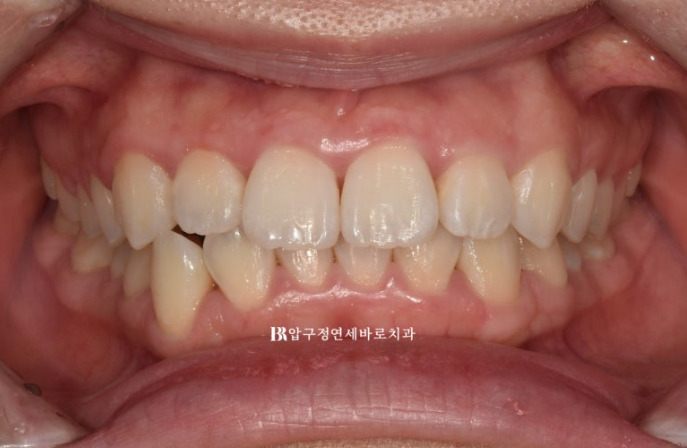

23.11

4달간 인비절라인라이트에서 가능한 14개의 장치를 모두 낀 후 모습입니다.

7일에 하나씩 교체할 경우 14개의 장치를 다 끼면 약 4달의 시간이 흐릅니다.

배열이 잡혀 가지런해졌으나

송곳니 반대교합이 아직 남아있고 중심선이 개선이 되긴 했으나 완벽하게 맞지 않습니다.